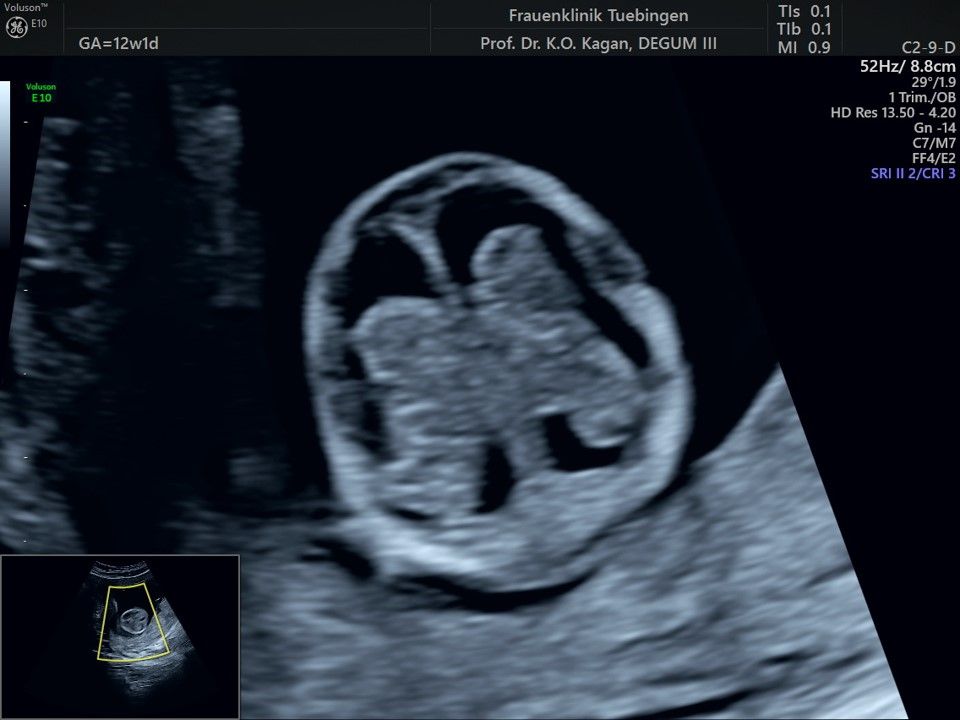

Im Rahmen des Ersttrimester-Screenings untersuchen wir die Organe des Feten mittels Ultraschall. Dabei machen wir auch gerne ein Bild für Sie.

Obwohl der Fet zu diesem Zeitpunkt erst zwischen 5 und 8cm groß ist, lassen sich bereits etwa die Hälfte aller schwerwiegenden Fehlbildungen erkennen bzw. ausschließen. Sollten wir eine Auffälligkeit sehen, werden wir mit Ihnen den Befund und das weitere Vorgehen ausführlich besprechen.

Fetale Anatomie

Das Ergebnis der Ultraschalluntersuchung ist wegweisend. Dabei wird der Fet vermessen, die Organe werden untersucht und die sonographischen Marker zur Risikoberechnung für Chromosomenstörungen werden beurteilt. Das sind: die Nackentransparenzdicke, Nasenbein sowie der Blutfluss in der rechten Herzhälfte und im Ductus venosus, einem Gefäß in der Leber des Feten.